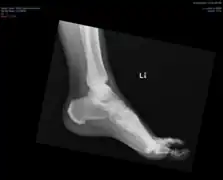

In some, the x-ray findings may correspond to symptoms of back stiffness with flexion/extension or with mild back pain.[2] Back pain or stiffness may be worse in the morning.[4] Rarely, large anterior cervical spine osteophytes may affect the esophagus or the larynx and cause pain, difficulty swallowing[5][6] or even dyspnea.[7] Similar calcification and ossification may be seen at peripheral entheseal sites, including the shoulder, iliac crest, ischial tuberosity, trochanters of the hip, tibial tuberosities, patellae, and bones of the hands and/or feet.[6]

DISH is diagnosed by findings on x-ray studies. Radiographs of the spine will show abnormal bone formation (ossification) along the anterior spinal ligament. The disc spaces, facet and sacroiliac joints remain unaffected. Diagnosis requires confluent ossification of at least four contiguous vertebral bodies.[2] Classically, advanced disease may have "melted candle wax" appearance along the spine on radiographic studies.[13] In some cases, DISH may be manifested as ossification, or enthesis, in other parts of the skeleton.